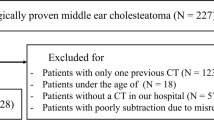

In center A, a database search was performed for patients who underwent initial unenhanced HRCT for clinically suspected cholesteatoma between January 2017 and September 2018. In center B, a retrospective review of surgery log books of January 2006 to January 2010 was performed to identify patients that underwent surgery due to suspected cholesteatoma or MEI. Final confirmation of diagnosis was based on intra-operative histology in all cases. In both centers, exclusion criteria were former surgery of the middle ear, no pathological findings in HRCT, and lack of preoperative HRCT or post-operative histology. In both centers, patients were included consecutively; neither in children nor in adults, size or other morphological criteria of the lesions on HRCT were used for patient selection.

In center A, 18 out of the initial group of 68 patients were excluded due to former surgery of the middle ear (n = 15) or lack of pathological findings in HRCT (n = 3). All remaining 23 patients received surgery after HRCT and were histologically diagnosed with cholesteatoma. Another 27 patients with histological or clinical diagnosis of MEI were used as a control group. Mean patient age was 33.1 ± 19.9 (range, 6–78 years); 38 patients were male.

In center B, 69 consecutive patients who underwent surgery due to cholesteatoma were retrospectively included. Out of these patients, 44 had to be excluded due to lack of preoperative HRCT (n = 42) or post-operative histology (n = 2). Another 25 patients with MEI were retrospectively selected as a control group. Mean age was 39.5 ± 22.3 years (range, 5–81 years); 24 patients were male.

Thus, 100 patients (center A, 50 patients, 23 with cholesteatoma, 27 with MEI; center B, 50 patients, 25 with cholesteatoma, 25 with MEI) were included in this study (Fig. 2).